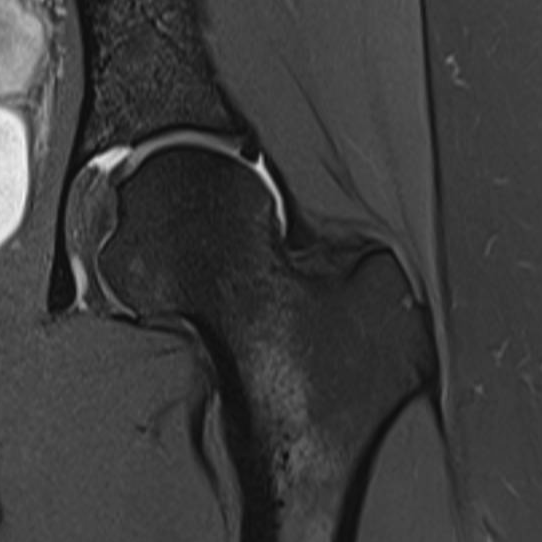

Se você sente dor no quadril, especialmente ao praticar esportes ou realizar movimentos específicos, pode estar lidando com o Impacto Femoroacetabular (IFA)...